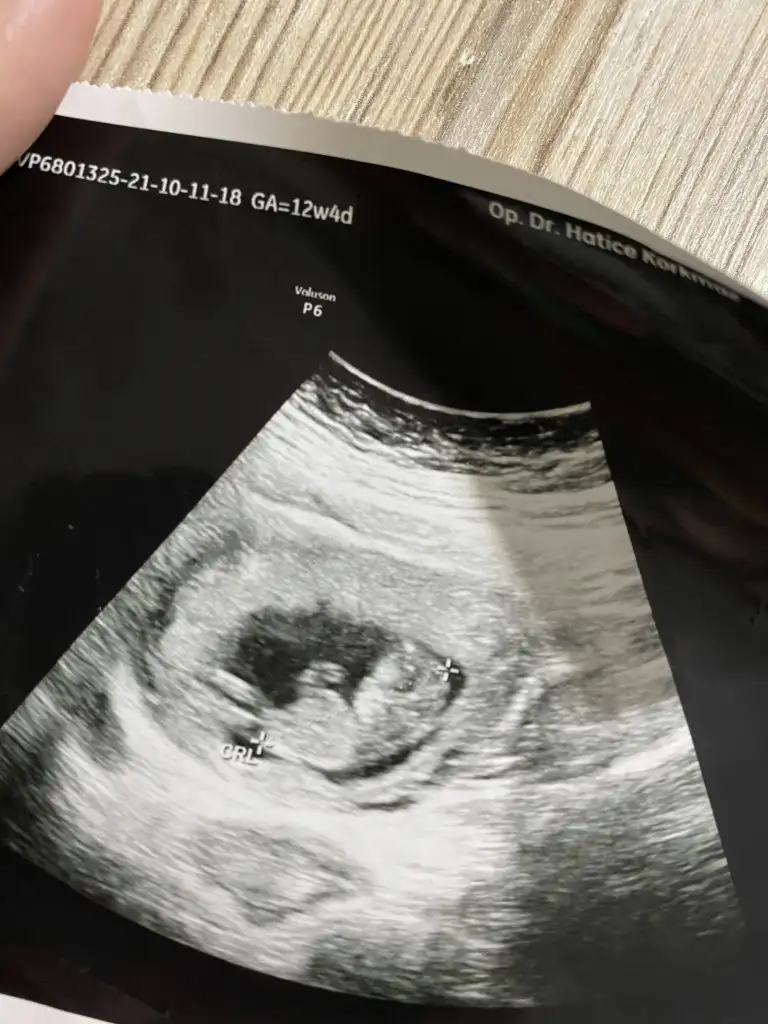

Kız benceYammelina90 iyi akşamlar benim küçük civcivin cinsiyeti belli oluyor muuuu?

Galibaaa kız. Bi çıkıntı gördüm gibi ama o çıkıntı poposuna paralel ise kız yukarı doğruysa erkekmiş. Paralel galiba. Benim civcivim kız sanırsamKız bence

Saglikla kucağınıza alırsınız insallah13 bugün bitti 14e giriyorum.